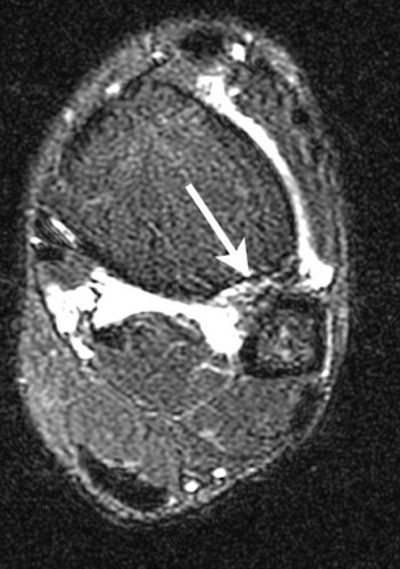

| Axial FSEIR at the tibial plafond shows rupture of the anterior and posterior tibiofibular ligaments, and the interosseous membrane (arrow). |